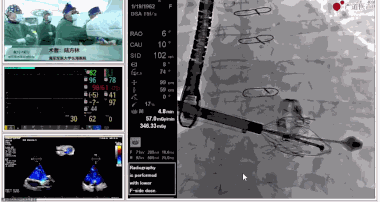

▲瓣膜植入前右心室造影

▲瓣膜植入過程